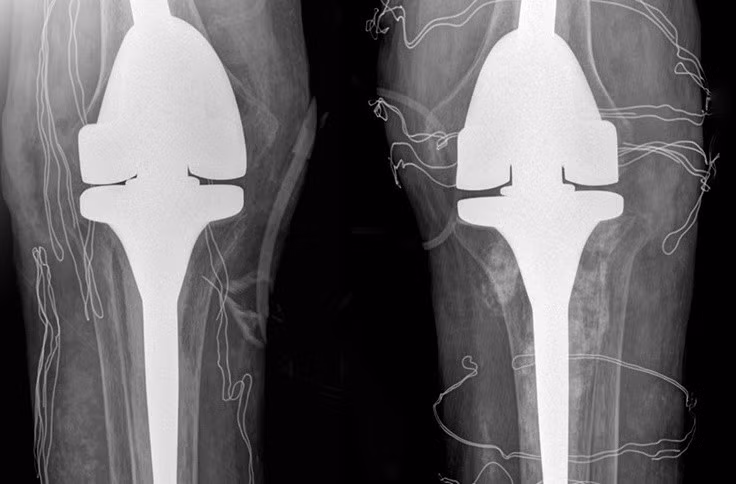

ThS.BS Nguyễn Quang Tôn Quyền, Phó khoa Chấn thương Chỉnh hình, Bệnh viện Đa khoa Tâm Anh Hà Nội chẩn đoán, bệnh nhân mất khả năng duỗi khớp gối, chỉ co được 60-70 độ, chụp X-quang cho thấy hai khớp gối bệnh nhân biến dạng nặng, tổn thương tophi khiến khớp và xương tiêu. Kiểm tra loại “thuốc” mua trên mạng mà anh T. uống, bác sĩ phát hiện là sản phẩm hỗ trợ sức khỏe đã bị Cục Quản lý Thực phẩm và Dược phẩm Mỹ (FDA) cảnh báo chứa chất dexamethasone gây nguy hiểm.

Phim chụp X-quang hai bên khớp gối nhân tạo của bệnh nhân. Ảnh: Bệnh viện Đa khoa Tâm Anh.